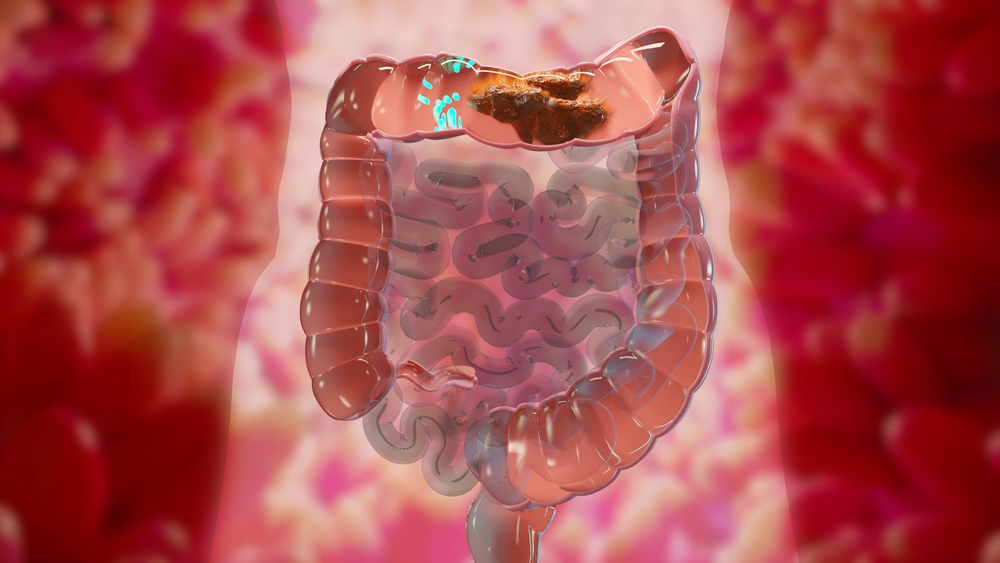

۳. انسداد روده

در موارد شدید، مدفوع فشرده و خشک ممکن است راه خروجی روده را مسدود کند. این وضعیت که به آن «انسداد مدفوعی» گفته میشود، میتواند نیازمند مداخلات پزشکی فوری مانند تنقیه یا حتی جراحی باشد.